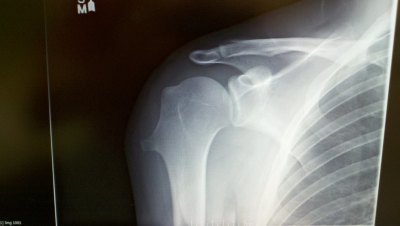

Found out why my shoulder has been hurting since baseball in Middle and High School... I damaged my growth plate back then, and it did some crazy growing for a few years it looks like....

2012061316.jpg

Its supposed to look like this...